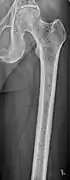

X-ray of the forearm, with lytic lesions

The diagnostic examination of a person with suspected multiple myeloma typically includes a skeletal survey. This is a series of X-rays of the skull, axial skeleton, and proximal long bones. Myeloma activity sometimes appears as "lytic lesions" (with local disappearance of normal bone due to resorption) or as "punched-out lesions" on the skull X-ray ("raindrop skull"). Lesions may also be sclerotic, which is seen as radiodense.[70] Overall, the radiodensity of myeloma is between −30 and 120 Hounsfield units (HU).[71] Magnetic resonance imaging is more sensitive than simple X-rays in the detection of lytic lesions, and may supersede a skeletal survey, especially when vertebral disease is suspected. Occasionally, a CT scan is performed to measure the size of soft-tissue plasmacytomas. Bone scans are typically not of any additional value in the workup of people with myeloma (no new bone formation; lytic lesions not well visualized on bone scan).

Bone pain affects almost 70% of people with multiple myeloma and is one of the most common symptoms.[2]: 653 [22] Myeloma bone pain usually involves the spine and ribs, and worsens with activity. Persistent, localized pain may indicate a pathological bone fracture. Involvement of the vertebrae may lead to spinal cord compression or kyphosis. Myeloma bone disease is due to the overexpression of receptor activator for nuclear factor κ B ligand (RANKL) by bone marrow stroma. RANKL activates osteoclasts, which resorb bone. The resultant bone lesions are lytic (cause breakdown) in nature, and are best seen in plain radiographs, which may show "punched-out" resorptive lesions (including the "raindrop" appearance of the skull on radiography). The breakdown of bone also leads to the release of calcium ions into the blood, leading to hypercalcemia and its associated symptoms.[23]